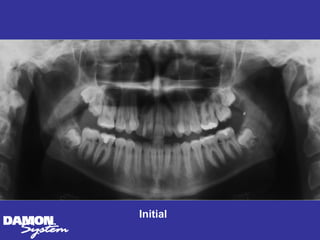

Initial 16 yearsโ€“ 5 months Class II, severe crowding, bilateral posterior crossbite

Treatment Planning โ€ข Ceph numbers โ€ข Model analysis โ€ข Pano X-rays โ€ข Facial analysis โ€ข Impact of growth/aging โ€ข Vestibular bone density โ€ข Tongue position/airway โ€ข How light a wire do I need to stimulate blood flow?